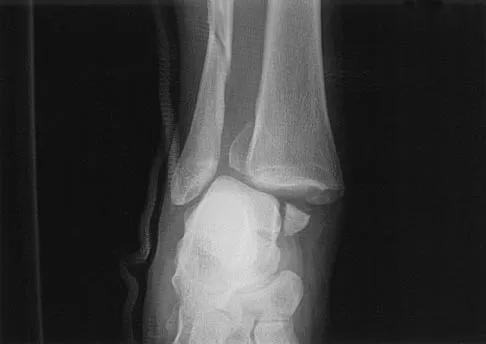

A 24-year-old woman was struck by a mini van in a parking lot and sustained a closed segmental tibia fracture that was treated with an intramedullary nail the following morning. Follow-up examinations reveal a slowly progressive clawing of all five toes, a progressive equinocavovarus contracture, and the patient is unable to perform a single heel rise on the affected limb. At 1 year after surgery, the patient now has a 10-degree equinus contracture that is not relieved with knee flexion. Treatment should now consist of

Explanation

This is an example of a missed deep posterior compartment syndrome that typically presents 6 months after the injury with progressive clawing due to necrosis, scarring, and contracture of the posterior tibial tendon, flexor digitorum longus, and flexor hallucis longus. Treatment consists of debridement of necrotic muscle and scar tissue with corresponding tendon excision. After debridement and posterior capsule release, if the equinus is relieved with knee flexion, a gastrocnemius slide may be performed. Otherwise, the lengthening should be at the level of the Achilles tendon. Bracing will not address the claw toes. Hansen ST Jr: Functional Reconstruction of the Foot and Ankle. Philadelphia, PA, Lippincott Williams & Wilkins, 2000, pp 212-213. Manoli A II, Smith DG, Hansen ST Jr: Scarred muscle excision for the treatment of established ischemic contracture of the lower extremity. Clin Orthop Relat Res 1993;292:309-314.